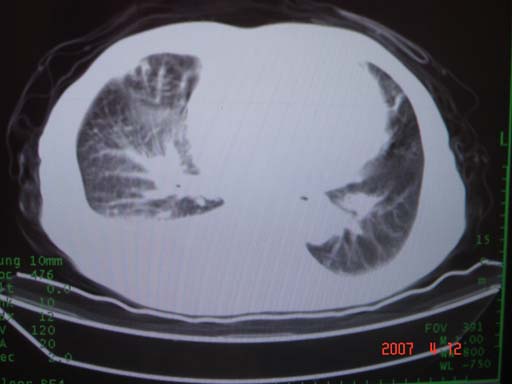

帮我 看看。男77岁咳嗽咯血2月发热2周!病人一般情况可 口痰为鲜红,有点象洗肉水(我看见他吐的痰了)

为何只有这么几幅图像?连纵隔窗都没有。但我发现上叶支气管显示不清,再加上年纪大,咯血等症状,恶性肿瘤首先得考虑。

考虑右肺新生物伴右中上肺阻塞性肺炎及含气不良,右侧胸腔积液。建议痰与纤支镜检查

考虑右侧中央型肺癌伴中上肺阻塞性肺炎、不张,胸腔积液。,建议支纤镜检查。

考虑:右上肺癌伴中上叶炎症,右侧胸腔积液。

病灶局限在右肺中上叶,呈大片状实变影,内见空气支气管征,支气管分支较柔软,纵隔内未见肿大淋巴结.支持:感染性病变_1 大叶性肺炎.2 干酪性肺炎.

优先考虑右上肺干酪性肺炎并同侧中叶播散、胸腔积液。分析:右膈肌未见升高、纵隔未见明显右移,胸部各组淋巴结未见可疑肿大,中叶可见支气管铸形,肺野、肺门未见可确定肿块。

右肺上叶后段支气管中断,首先考虑中央型肺癌并右肺不张及纵隔淋巴结转移,右侧胸腔积液。

有点象洗肉水的痰,其来源应当是实变引起的血细胞渗出导致,可见支气管气象,实变区有虫蚀状空洞,有明显胸腔积液,未见明显肺门区肿块影,考虑继发型肺结核,干酪性肺炎

右肺上叶实变,实变范围如此之大,如果用肺癌解释的化,应该是比较大的支气管开口发生完全阻塞,但观察上叶前后段支气管还是比较通畅,所以应考虑感染性病变,大叶性肺炎可能,建议抗炎治疗后复查。